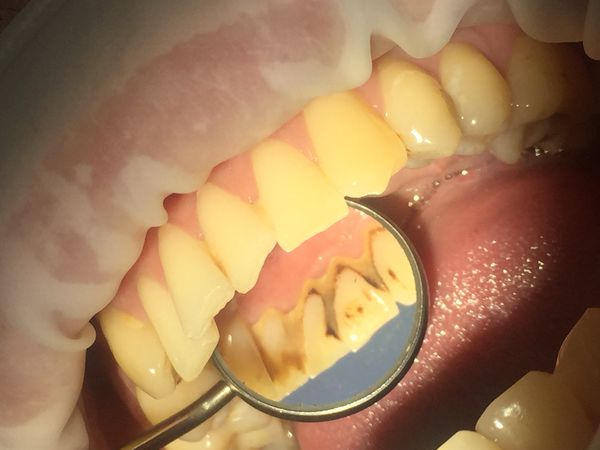

При осмотре полости рта был выявлен мягкий пигментированный зубной налёт на всех зубах верхней и нижней челюсти на язычной и нёбной поверхностях. В области передних зубов с язычной стороны визуализировался твёрдый пигментированный зубной камень. Десна и межзубные сосочки были гиперемированы (т. е. имелось покраснение) и воспалены в области всех зубов.

При осмотре с помощью стоматологического зеркала и зонда был обнаружен твёрдый зубной камень на жевательных зубах верхней и нижней челюсти справа. Непигментированный камень покрывал всю щёчную поверхность жевательных зубов верхней челюсти, при зондировании с трудом откалывался от поверхности зуба. К тому же зубной камень в области жевательных зубов верхней челюсти погружался под десну, тем самым образуя патологический карман между десной и зубом и провоцируя воспаление десны с язычной стороны. При окрашивании зубов специальными индикаторами для выявления зубного налёта был обнаружен непигментированный мягкий зубной налёт на всех зубах с вестибулярной стороны (со стороны щеки и губ).